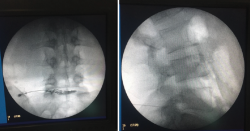

Constituye una evaluación radiológica (bajo control fluoroscópico) y fisiológica del disco intervertebral mediante, la inyección intradiscal de un medio de contraste, ya sea por vía intra- o extradural. Hay que tener en cuenta la cantidad de contraste que ha sido inyectado, la presión de inyección, el aspecto radiológico del disco inyectado y, por último, la reproducción de dolor durante la prueba.

La inyección de contraste en un disco intervertebral normal es habitualmente indolora y el contraste tiende a permanecer en el núcleo pulposo, por lo que se considerará positiva esta prueba cuando la inyección intradiscal provoca un dolor semejante al referido por el paciente y la morfología del discograma es anormal o se produce la extravasación del contraste utilizado.

Figura 15. Discografía.

La técnica consiste en pinchar oblicuamente con una aguja en el centro del disco e introducir un contraste radiopaco. El enfermo está despierto en todo momento. Con ese contraste radiopaco se produce una imagen clara de si el disco es o no patológico, pudiendo apreciar si el disco entre vértebra y vértebra está deshidratado, si la morfología es normal o diferente, si sale o no contraste, si hay dolor irradiado a ambas piernas o solo a una de ellas, y si ha notado o no dolor el paciente (Figura 15).

La discografía es utilizada como método diagnóstico del dolor discogénico, aunque varios metaanálisis demostraron una disminución de la tasa de falsos positivos del 0 al 10%. La discografía es una prueba subjetiva, confiando completamente en la experiencia de dolor del paciente durante la realización de este breve procedimiento. Entre los elementos que disminuyen la tasa de falsos positivos se encuentra la utilización de criterios de inclusión más estrictos y la monitorización de la presión intradiscal.

Por otra parte, es una técnica invasiva no exenta de efectos secundarios importantes, aunque infrecuentes: discitis, toxicidad del sistema nervioso central secundaria a la extravasación del contraste yodado en el espacio subaracnoideo, hemorragia intratecal, aracnoiditis, meningitis y afectación discal.

Sus condicionantes de falsos positivos, subjetividad y efectos secundarios han determinado una disminución importante en su utilización, quedando relegada su indicación de forma previa a la realización de una cirugía discal o de una fusión vertebral y en pacientes intervenidos quirúrgicamente con un fracaso de la fusión vertebral.